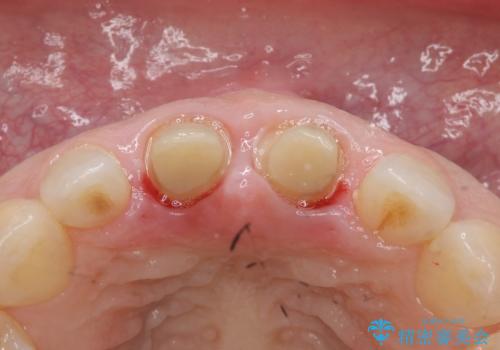

前歯を下げるために、上下左右の小臼歯を抜歯することになりましたが、すでに前歯の角度を不自然に作ってあるため、

もう一度前歯を元の角度に被せ直してから仮歯で矯正を行いました。

その後、マージンが舌側が深い状態だったため、歯ぐきの手術(歯周外科処置:APF)を行ってから最終的なセラミックを装着しました。